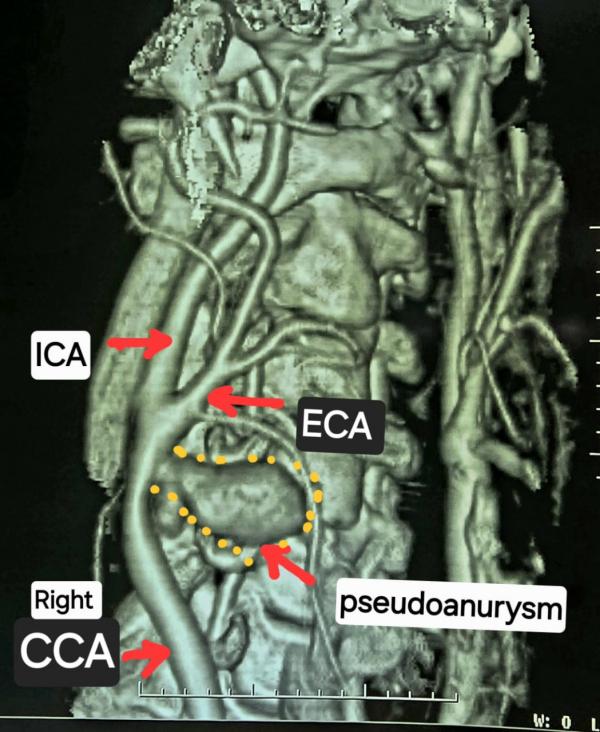

गर्दन के नसों की सीटी एंजियोग्राफी जांच में यह चौंकाने वाला तथ्य सामने आया कि मरीज की दायीं कैरोटिड आर्टरी फट चुकी है और उसके चारों ओर गुब्बारानुमा संरचना बन गई है, जिसे कैरोटिड आर्टरी स्यूडोएन्युरिज्म (Carotid Artery Pseudoaneurysm) कहा जाता है। स्थिति की गंभीरता को देखते हुए मरीज को तत्काल हार्ट, चेस्ट एवं वैस्कुलर सर्जरी विभाग में में डॉ कृष्ण कांत साहू के पास भेजा गया।

लगभग कई घंटे चले इस चुनौतीपूर्ण ऑपरेशन में बोवाइन पेरिकार्डियम पैच की सहायता से फटी हुई कैरोटिड आर्टरी को अत्यंत सावधानीपूर्वक रिपेयर किया गया। सर्जरी पूरी तरह सफल रही और राहत की बात यह रही कि मरीज को किसी भी प्रकार का लकवा नहीं हुआ। वर्तमान में मरीज पूरी तरह स्वस्थ है।